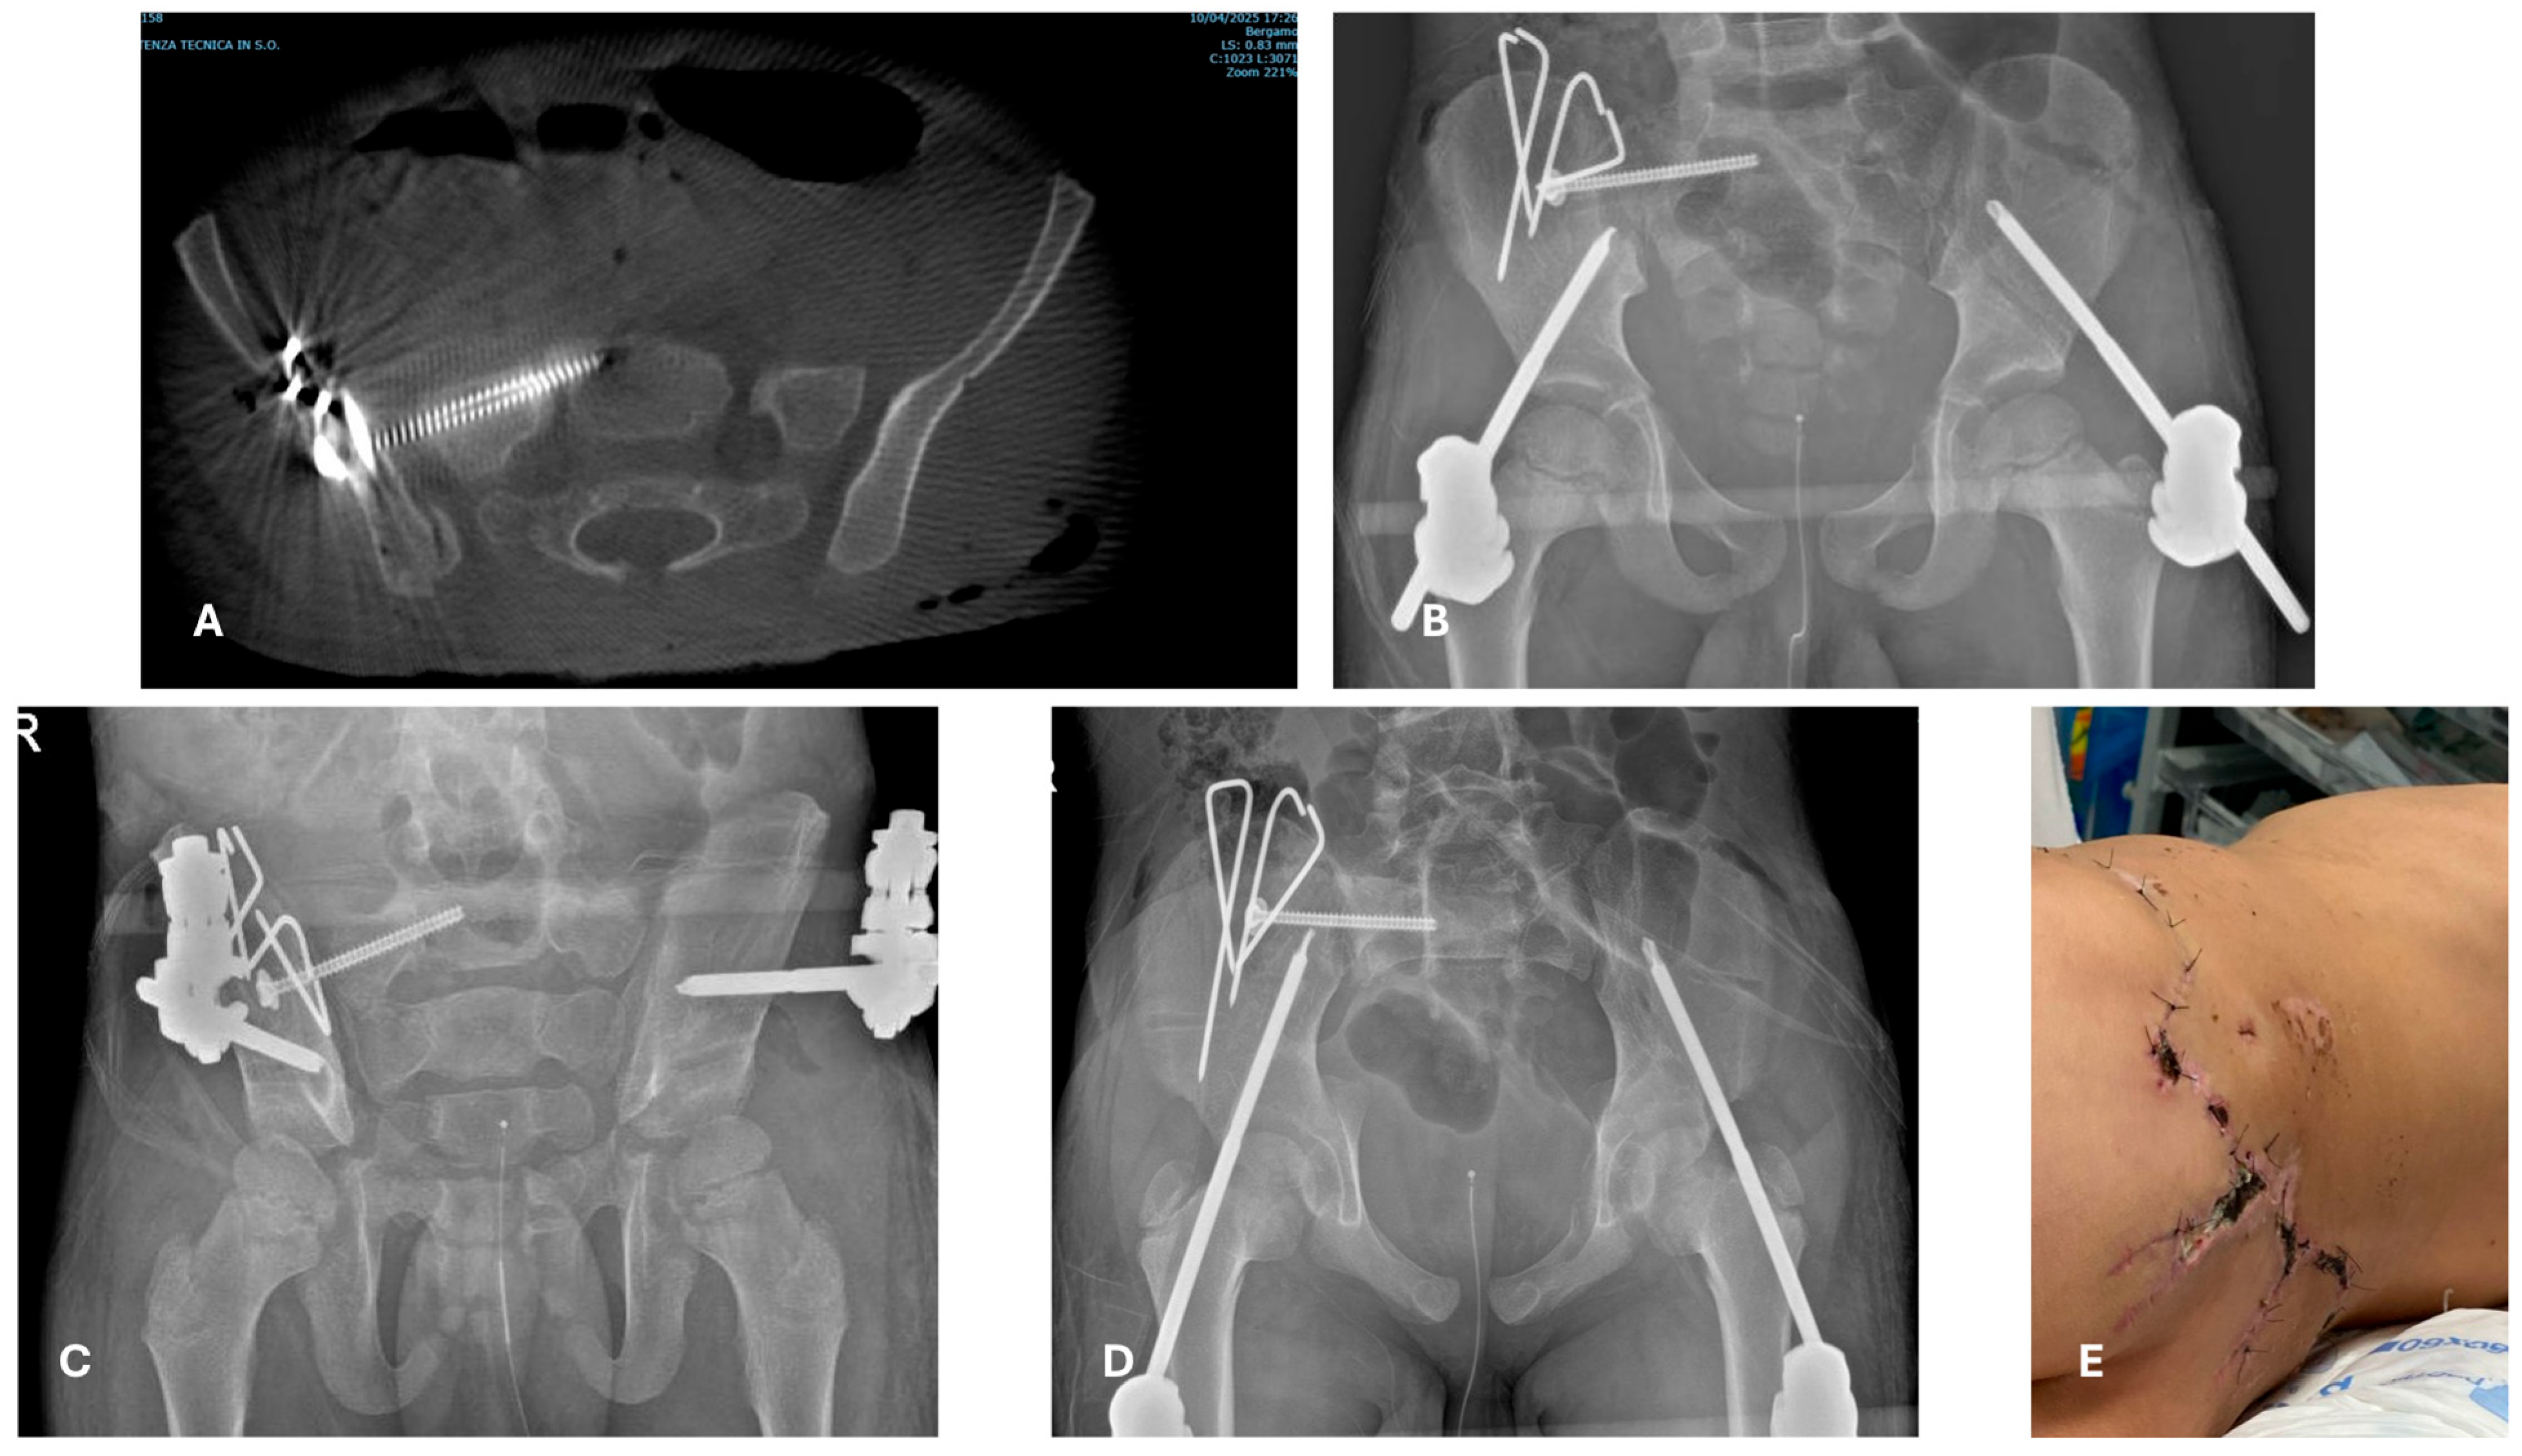

- In the age-group 15–17 years, 23/23 (100%) cases were treated with temporary external fixation (ExFix);

- In the age group 12–14 years, 9/14 (64%) cases were treated with ExFix, and 5/14 (26%) cases were treated with elastic stable intramedullary nails (ESIN);

- In the age group 5–11 years, 1/5 (20%) cases were treated with ExFix, and 4 cases were treated with ESIN;

- In the age group 0–4 years, 2/4 (50%) cases were treated with ESIN, and 2/4 (50%) cases were treated with a hip spica cast.